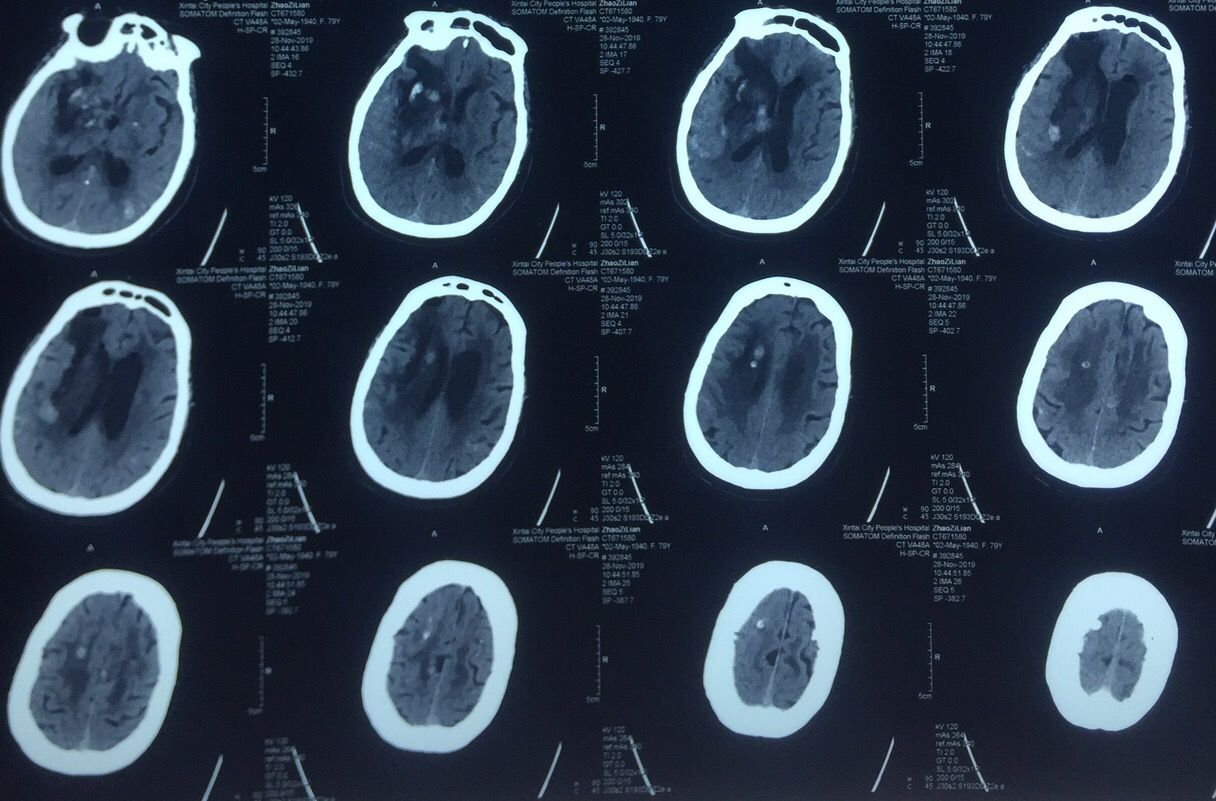

前后对比图如下↓↓↓

Kocher点的验证↓↓↓

从最后复查的骨窗位可以看到钻孔的位置

定位还算准确

脑窗还可以看到穿刺管的路径↑

总结:对基底节血肿来说,穿刺的位置并不拘泥于颞部或前额部,冠状缝前的额中回区域也是不错的选择,当然要根据具体的血肿形态而定。